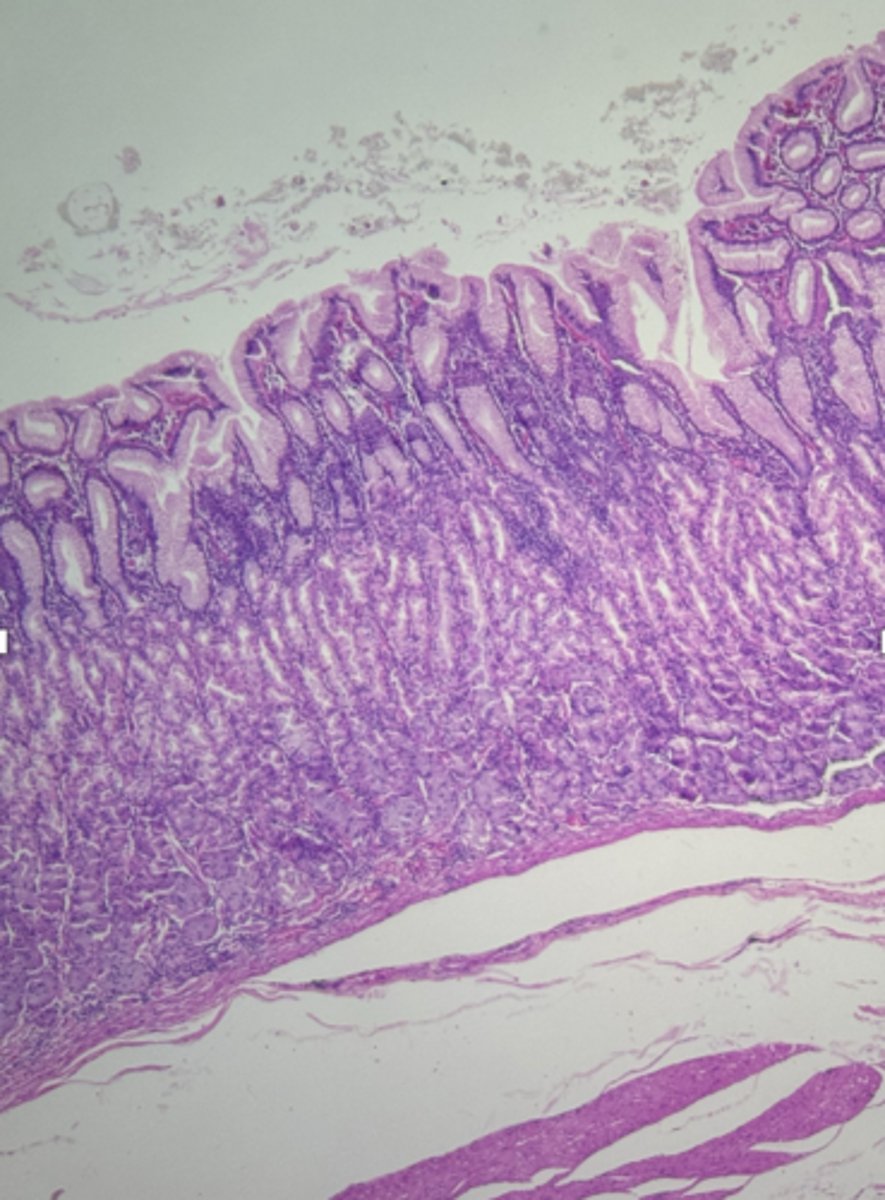

Duodenum (small intestine-cross section)

name the tissue

mucosa

(duodenum)

myscularis externa

Submucosa

Brunner's glands (KEY CHARACTERISTIC)

circular layer

longitudinal layer

Villi (KEY CHARACTERISTIC)

simple columnar epithelium

type of cell

intestinal crypts

lamina propria

muscularis mucosa